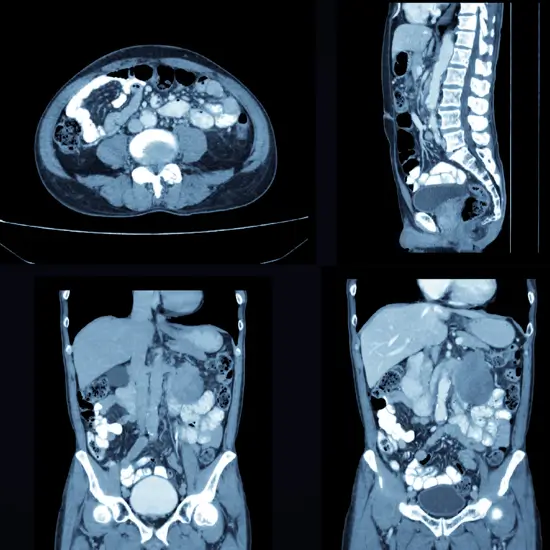

CECT (Contrast Enhanced Computed Tomography ) is an diagnostic scan that uses X-rays to create a detailed images of an abdomen in two-three phases- arterial, portal venous and delayed phase.

CECT (Contrast Enhanced Computed Tomography) Biphasic/Triphasic whole Abdomen is an imaging scan used to identify abdominal abnormalities. It creates cross-sectional images of abdominal structure at three different time points/phases. The abdominal structure includes the liver, kidneys, pancreas, spleen, GI Tract, and other organs.

CECT Scanning is often considered the best method for detecting the pain in abdomen, kidney stones, gallstones, infections and cancer.